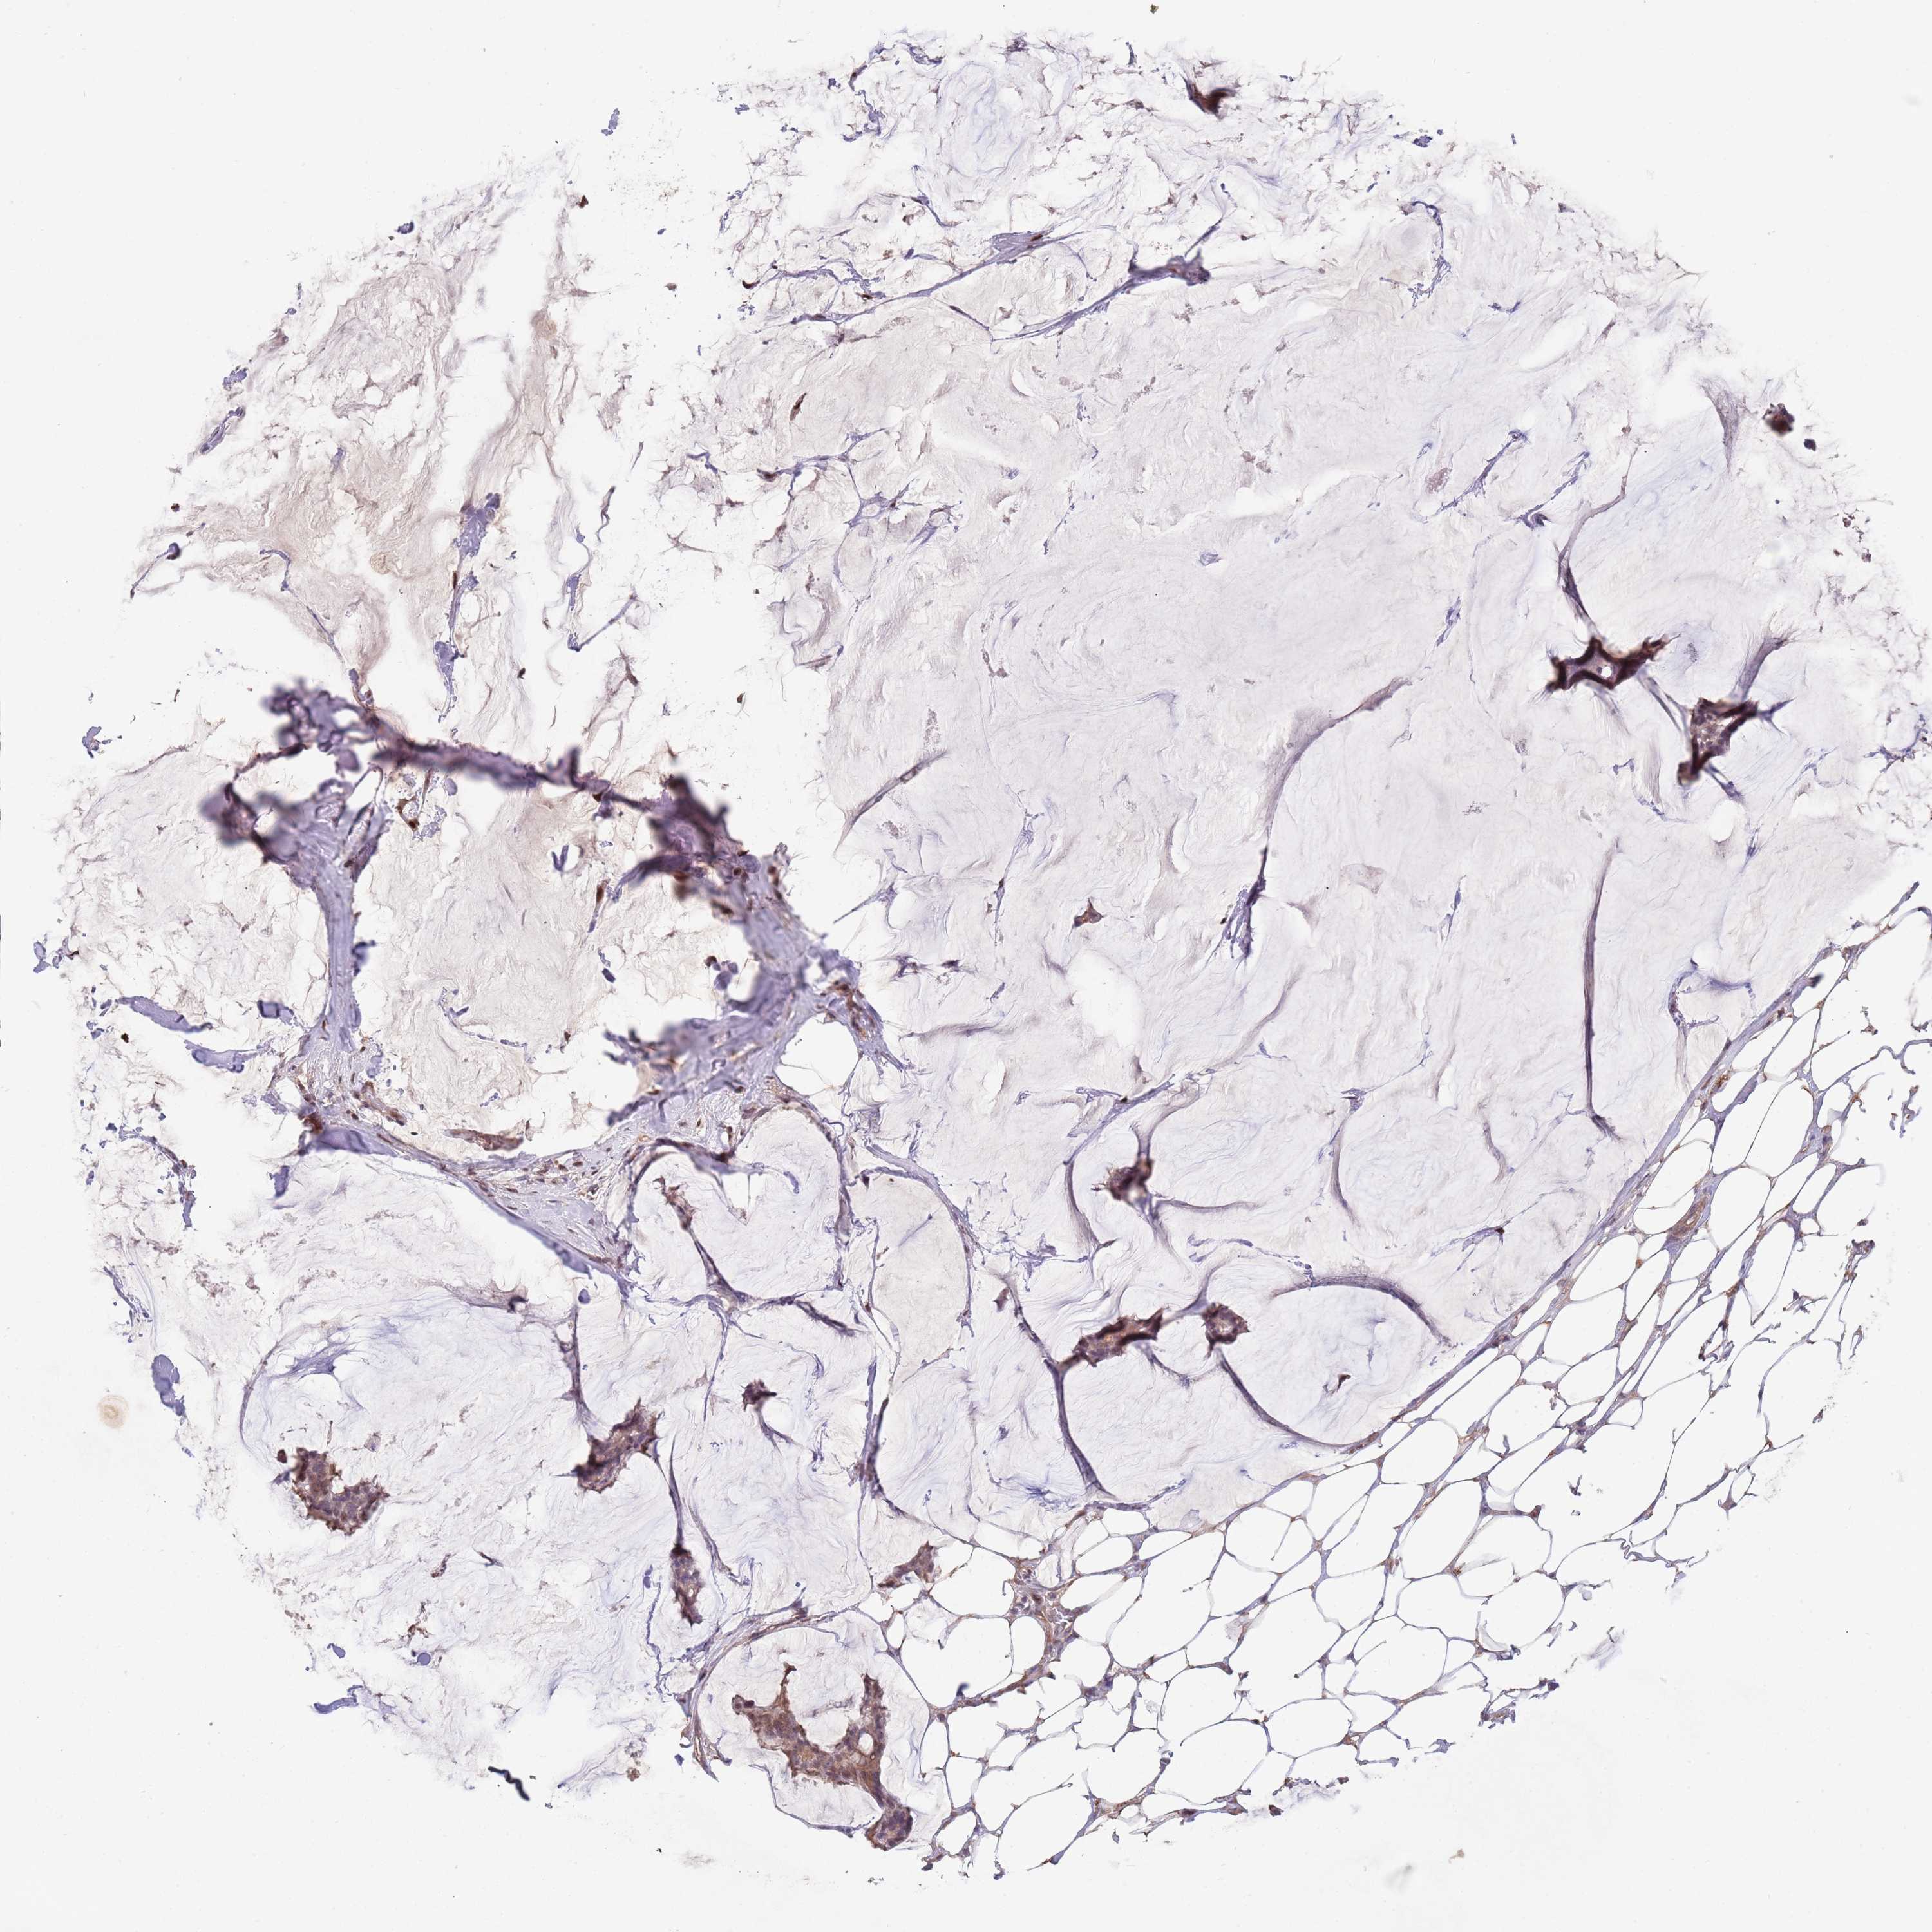

CANCER BREAST CANCER Show tissue menu

BRCA TCGA BRCA VALIDATION PROTEIN EXPRESSION

Breast cancer

Human cancer